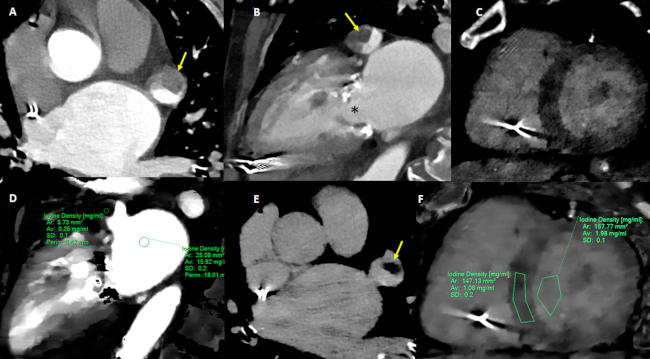

Caso 3. Se trata de una paciente de 74 años, con marcapasos definitivo y antecedente de ACVi hacía 5 años. Ingresó con hemiparesia izquierda y mareos (NI-HSS: 6) de 5 horas de evolución. La TC de cerebro con angio TC de vasos intra y extracraneanos y la perfusión evidenciaron oclusión a nivel de la arteria cerebral posterior derecha e hipoperfusión en territorio de la arteria cerebral posterior ipsilateral. La TC de tórax evidenció opacidades periféricas bilaterales en vidrio esmerilado (patrón indeterminado para COVID-19). Se realizó una angiografía cerebral, y se confirmó oclusión del segmento proximal de P1 derecha y, se procedió a realizar una trombectomía con stent retriever. Se obtuvo un TICI final modificado de grado 3. Evolucionó con edema agudo de pulmón hipertensivo (210/100 mmHg), con pro-BNP de 6700pg/ml y sin elevación de troponina, que requirió asistencia respiratoria mecánica por 24 horas. El ecocardiograma transtorácico reportó fracción de eyección del 55%, y no se identificaron trastornos regionales de la motilidad, y dilatación moderada de la aurícula izquierda. El Doppler de vasos de cuello no mostró lesiones significativas. El electrocardiograma mostró ritmo de marcapasos con sensado y captura adecuados que alternaba con ritmo de base de fibrilación auricular.. El hisopado para SARS-coronavirus 2019 fue negativo. Al cuarto día de internación se realizó una TC espectral cardíaca (Figura 3) para descartar FCE, y se identificó la presencia de un trombo en la orejuela izquierda y se procedió a realizar anticoagulación. Mediante un análisis espectral se descartó realce tardío de contraste y se calculó un VEC de 35%.